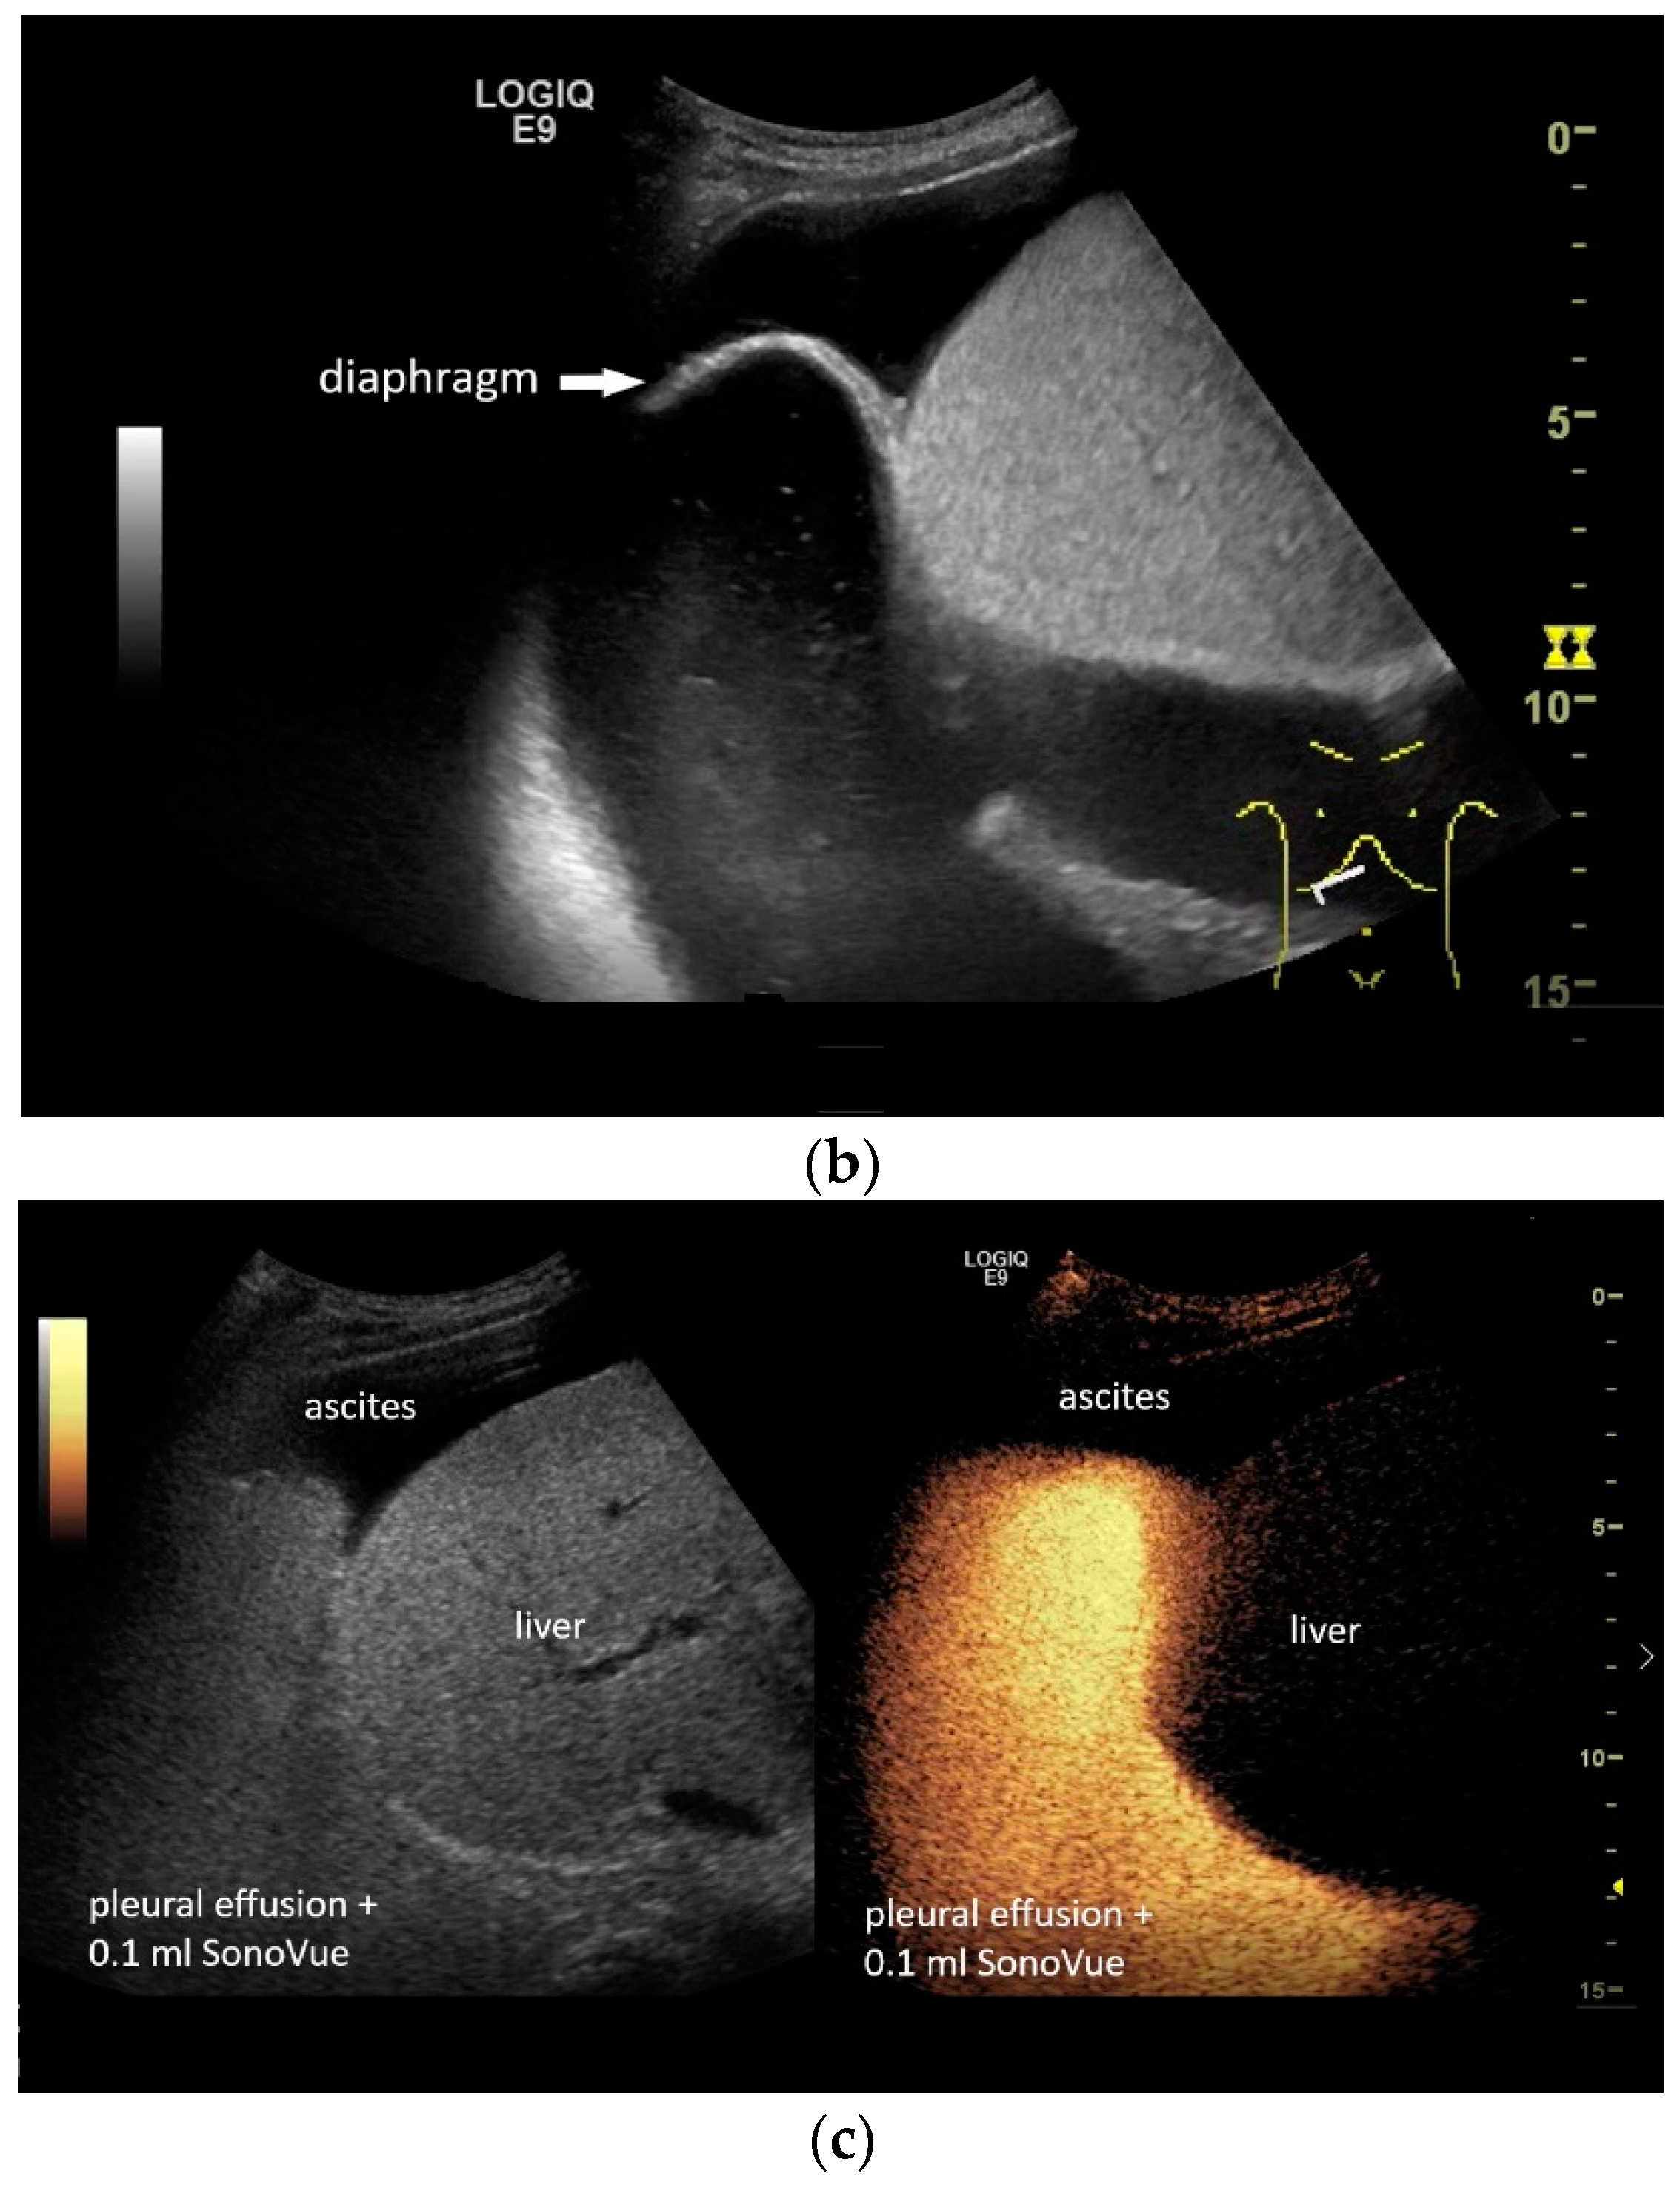

If a diaphragmatic fistula is suspected in cases of ascitic decompensated liver cirrhosis and concurrent unilateral pleural effusion, it is possible to use intracavitary CEUS to demonstrate the passage of the contrast agent from one cavity to the other. However, this is off-label use and usually the last diagnostic step (Figure 8).